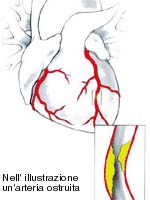

Il dolore anginoso � causato dal verificarsi di un'ischemia in una zona pi� o meno ampia della parete del cuore. Per ischemia si intende una riduzione transitoria dell'afflusso di sangue, e quindi dell'ossigeno e del nutrimento disponibile, o comunque uno squilibrio tra la domanda di ossigeno da parte del cuore e l�apporto di sangue che la circolazione riesce a fornire. Se il flusso sanguigno si arresta in modo irreversibile, invece, una parte del muscolo cardiaco muore, si cicatrizza e, in questo caso, si parla di infarto.

A causare l'ischemia � la presenza di placche di aterosclerosi sulla parete interna delle arterie del cuore, le coronarie. L�aterosclerosi � costituita da depositi di colesterolo, sui quali il sangue tende a coagularsi e a calcificarsi. La placca inizia a dar segno di s� quando restringe il diametro dell'arteria oltre il del 70 per cento: in queste condizioni la quantit� di sangue che passa � sufficiente a riposo (non ci sono sintomi), ma diventa insufficiente durante uno sforzo (angina da sforzo). Se il calibro dell'arteria � molto ristretto (pi� del 95 per cento) il sangue che riesce a passare pu� non essere sufficiente neppure a riposo (angina a riposo).Esiste poi una particolare variante di angina a riposo chiamata di Prinzmetal (dal nome di chi l�ha scoperta) che � dovuta a spasmi delle coronarie che nella maggior parte dei casi sono perfettamente normali, prive cio� di restringimenti fissi significativi. Caratteristica di questi casi � che lo spasmo, e quindi il dolore, tendono a comparire sempre nelle stesse ore della giornata e indipendentemente da qualunque attivit� del soggetto, spesso durante il sonno.